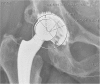

Material and methods: Twenty-eight patients with 34 consecutive early acetabular revisions were evaluated on failure mechanism. One type of implant was used in all cases. Standard pelvic radiographs and pre-operative CT scans were used to quantify PE wear, implant positioning and acetabular bone defects.

Results: An acetabular revision with impaction grafting was performed in all cases with a mean cup survival of ten years (range 1.3-19.3). No concurrent stem revisions were necessary. Overall implant positioning was adequate with a mean cup inclination of 45° (range 39-57) and anteversion of 25° (range eight to 45). The mean PE wear was 0.24 mm/year (range 0.00-1.17). The mean acetabular bone defect on pelvic CT scans was calculated as 352 mm² (range zero to 1107) and 369 mm² (range zero to 1300) in the coronal and transversal planes, respectively. A hooded acetabular insert was retrieved in all cases and profound PE wear, typically from the posterior hooded rim, was encountered.